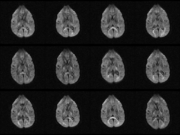

| 02:17, 18 December 2006 | 01-dwi-z20.png (file) |  |

381 KB | Image import script | Importing image file | 1 |